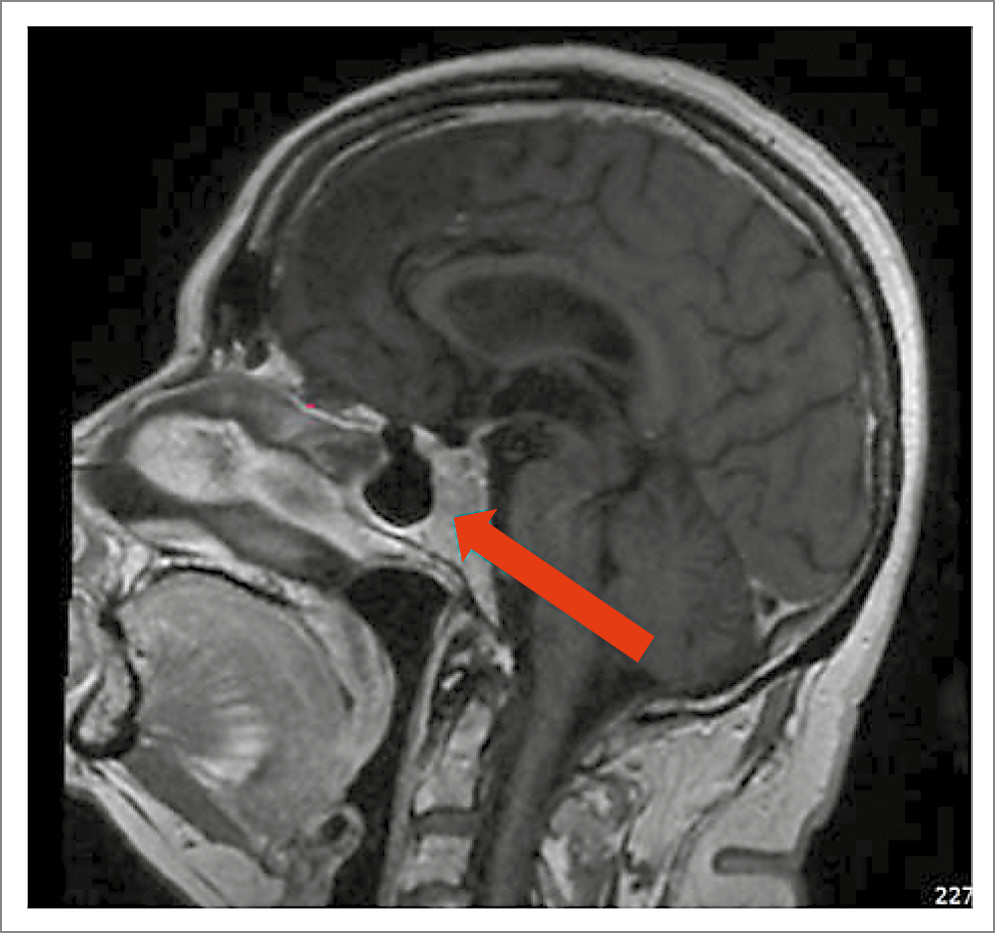

По данным лабораторного обследования подтвержден ЭГ: кортизол в ночном подавляющем тесте с 1 мг дексаметазона – 458 нмоль/л (< 50), кортизол слюны в 23:00 – 10,37 нмоль/л (< 9,4), суточная экскреция кортизола с мочой > 200 мкг/сутки (1,5–63). Уровень АКТГ составил 14,7 пмоль/л (0–10,2), что подтвердило АКТГ-зависимый генез заболевания. Проведена магнитно-резонансная томография (МРТ) головного мозга (рис. 1), выявлен очаг замедленного накопления контрастного препарата слева от средней линии размером до 4 мм – микроаденома гипофиза.

Рис. 1. МРТ головного мозга от 21.03.2023: микроаденома гипофиза.

С учетом небольшого размера выявленного образования (< 6 мм), в рамках дифференциальной диагностики АКТГ-зависимых форм ЭГ проведена большая дексаметазоновая проба, по результатам которой получено снижение кортизола на 80% от исходного уровня (кортизол в 8:00 исходно – 662 нмоль/л, кортизол в 8:00 после приема на ночь 8 мг дексаметазона – 132 нмоль/л). Результаты пробы свидетельствовали в пользу центрального генеза гиперкортицизма – БИК. Пациентка была направлена на консультацию нейрохирурга, в рамках предоперационной подготовки назначен обратимый ингибитор стероидогенеза кетоконазол 400 мг/сут.